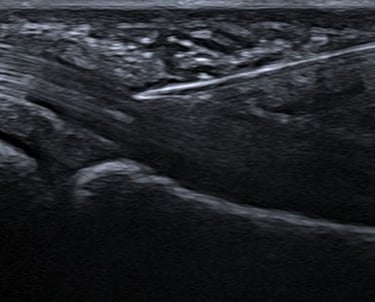

✔ Contrôle échographique en temps réel

Repérage précis à l’échographie

Ponction du liquide (si nécessaire)

Infiltration ciblée du traitement